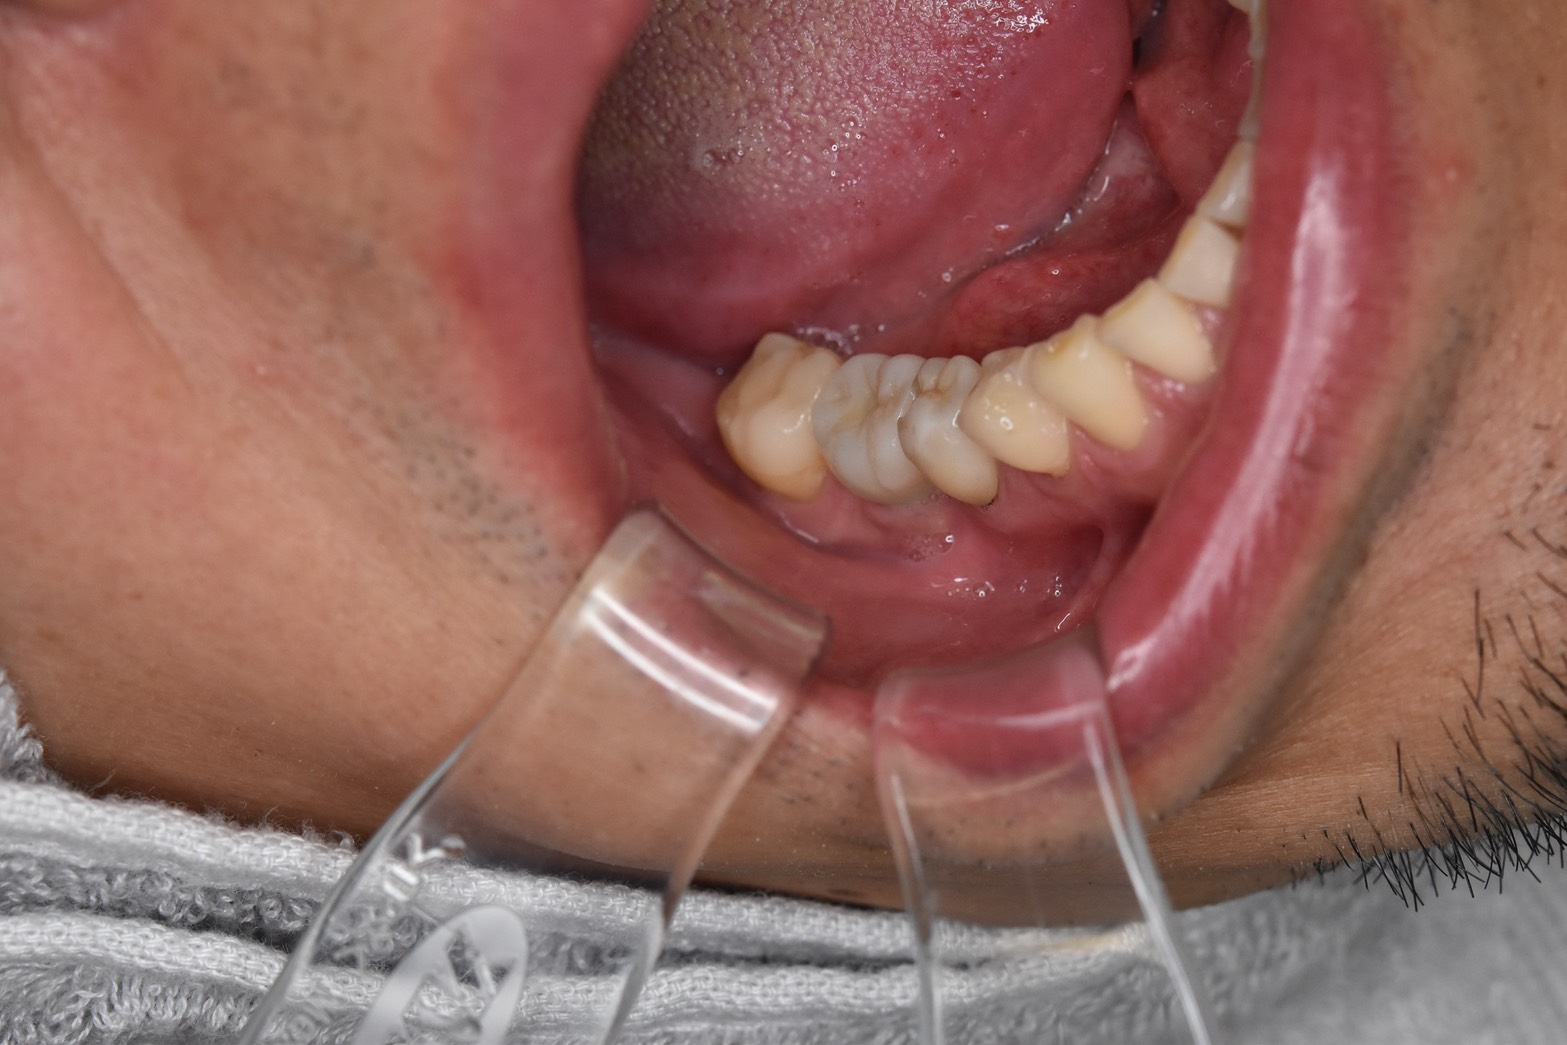

インプラント症例(60代男性)奥歯欠損の術前口腔内写真。ブリッジとインプラントで検討したケース

Before